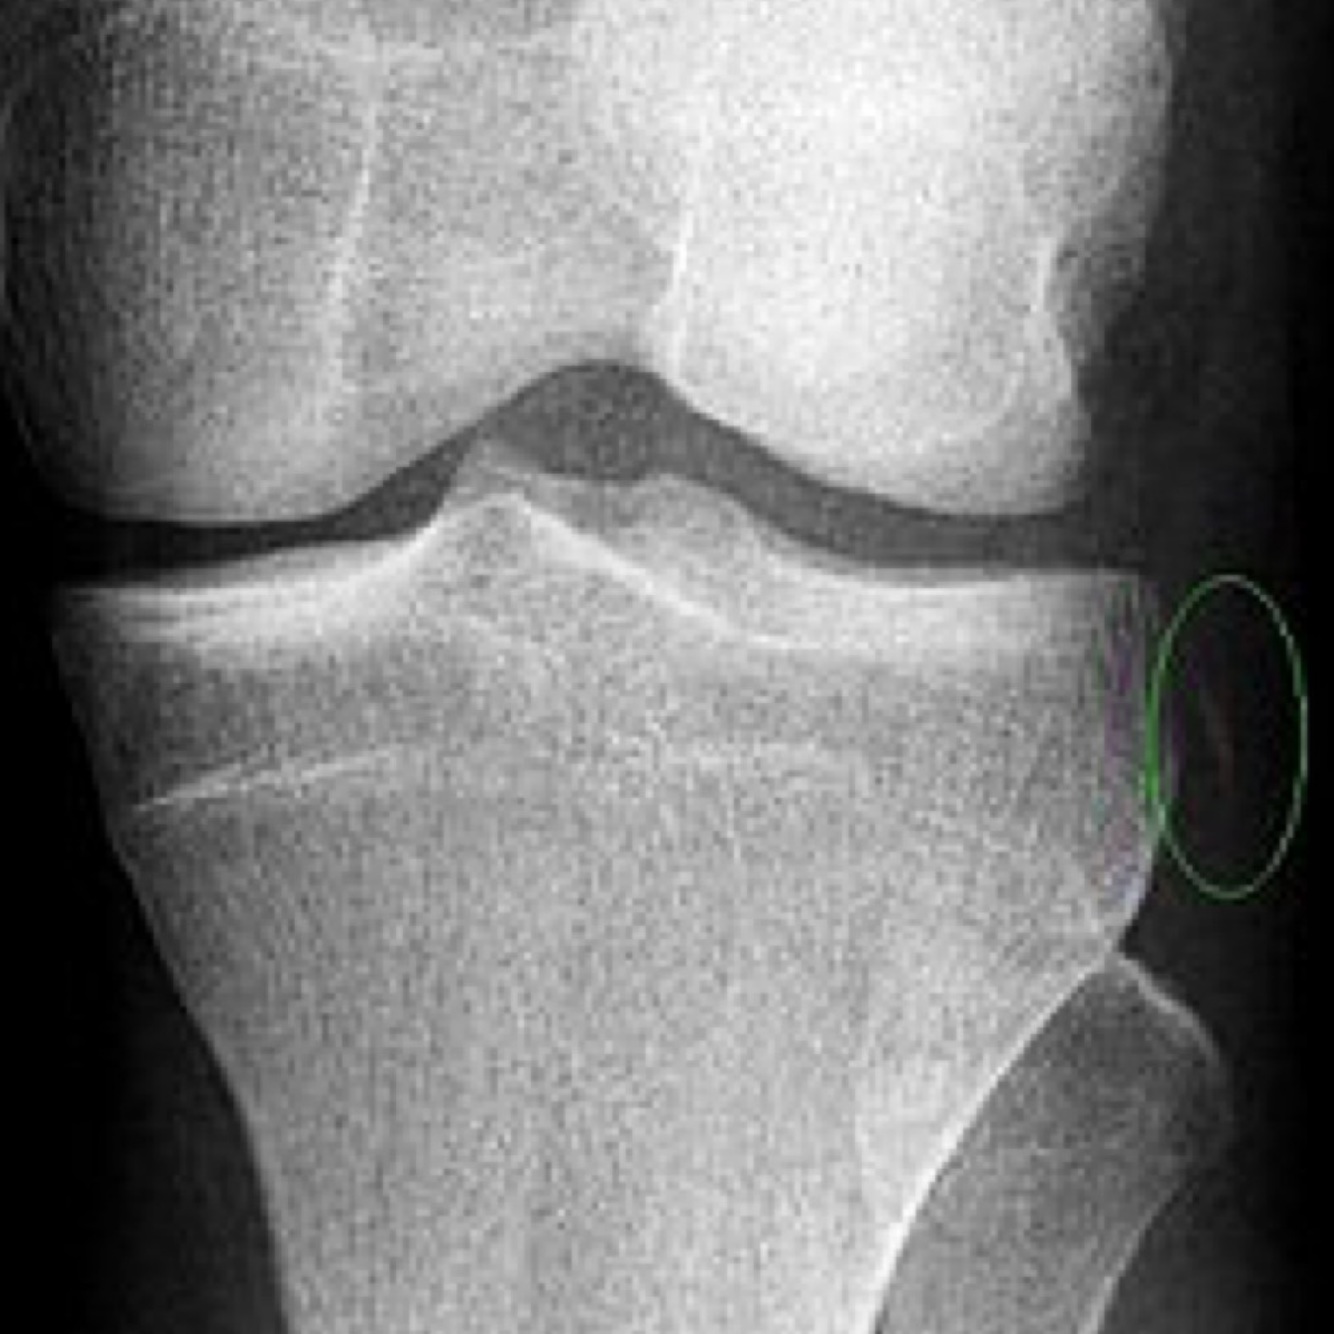

Qui suis-je?

Fracture de Segond 🦓

• Fracture avulsive en latéral du tibia sous le plateau tibial

• Hautement associée avec une déchirure du LCA, des ménisques, des structures postérieures du genou et de la capsule LAT

• Stress en varus et rotation tibiale INT